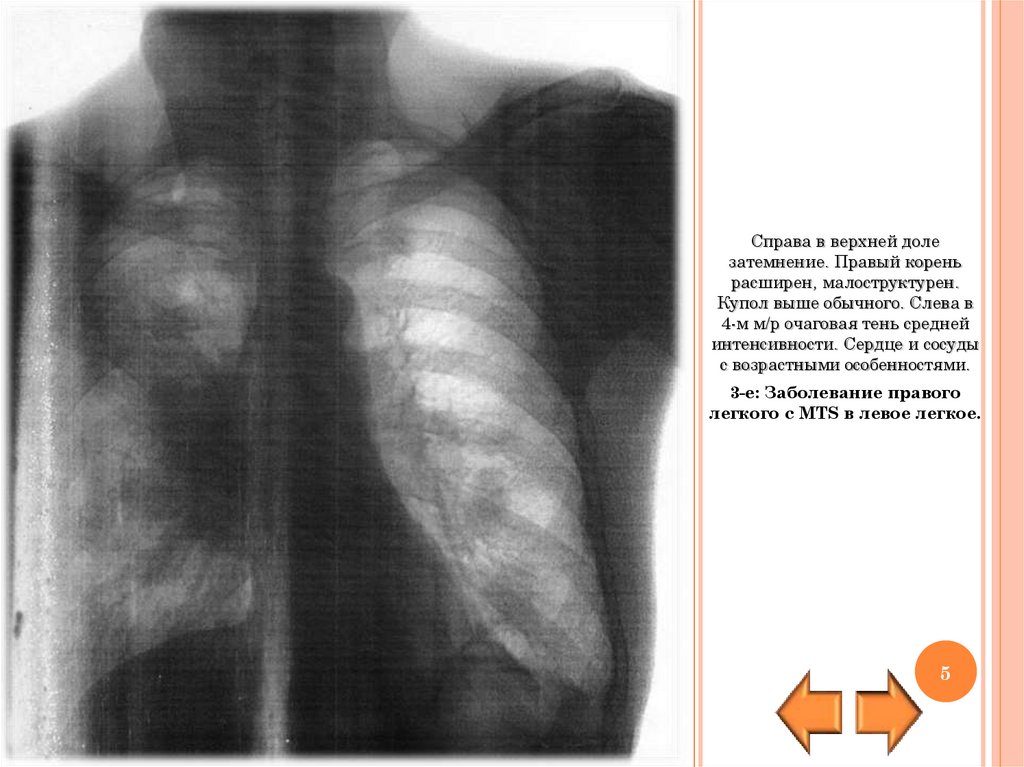

Справа в верхней доле

затемнение. Правый корень

расширен, малоструктурен.

Купол выше обычного. Слева в

4-м м/р очаговая тень средней

интенсивности. Сердце и сосуды

с возрастными особенностями.

3-е: Заболевание правого

легкого с MTS в левое легкое.